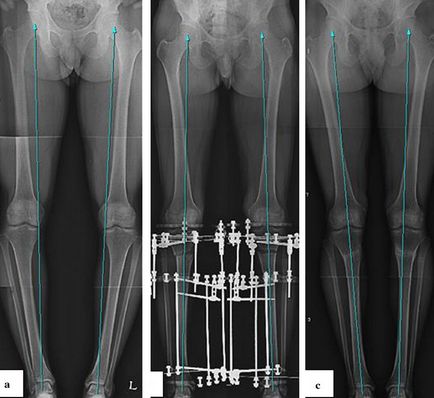

Javítás Az alsó végtag, amikor varus deformitás tengelye által Ilizarov berendezés

Csontösszekötő által Ilizarov

Ilizarov berendezés - a leggyakoribb módszer korrigálására súlyos komplex végtag deformitások. Nincsenek korlátozások a korrekció mértéke vagy korrekciója a deformáció más síkon. Együtt a megszüntetése szögletes deformitás teheti medialization, forgatni, távolítsa el a subluxation fibula fej és meghosszabbítsák a lábait. Teljes terhelés természetesen lehetőség van a következő néhány nappal a műtét után.

A fő komplikáció, amely akkor következik be, ha egy külső csontképződés - gyulladás helyenként küllők kilép. Ezek nem jelentenek nehézséget kezelésre. Az előfordulási osteomyelitis küllős nem haladja meg a 1,5%. Annak ellenére, hogy a gyulladásos folyamat vesz részt a csont, ez a folyamat a helyi gyógyítható teljesen.

A fő hátránya a Ilizarov készülék -, hogy az ő puszta jelenléte, a korlátozások a kiválasztásban, a ruházat és lábbeli. A megoldás erre a problémára az átmenet a gyűrű alakú támogatja a egyoldali mini rögzítőket elhelyezett elülső felülete a sípcsont. Ezek jóval kisebb méretűek, és nem akadályozzák a teljes funkció a térdízület.

Megjelenése beteg a mini-egységet a sípcsont során a deformáció korrekciója sípcsont

A megjelenése betegek varus deformitás mindkét lábszára használatával mini-bilincs

Az átmenet a gyűrűt a Ilizarov mini rögzítőket célszerűnek 1,5-2 hónappal a műtét után, ha vannak jelei a kialakulását a regenerátumot az osteotomia területen. A műveletek mindkét lábát mini bilincsek lehetővé teszik, hogy lezárja a lábát a térd és értékelje a végleges formája a láb még beállta előtt teljes varrás.